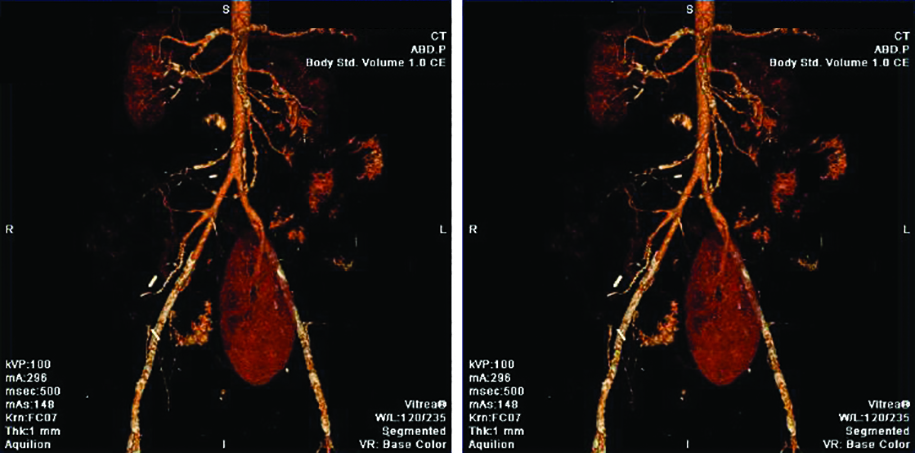

Fig. 8. TC post operatoria, un mes posterior a la cirugía.

En la segunda tomografía control efectuada se evidenció una disminución en el calibre de la anastomosis arterial, lo que se correlacionó con vasculitis. Con posterioridad a las complicaciones descritas, el paciente presentó los siguientes niveles de laboratorio: glucemia de 88 mg/dl y creatinina de 1.34 mg/dl.